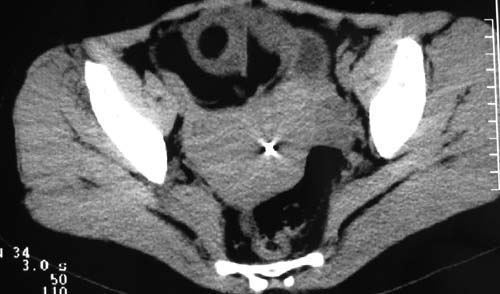

二、男,55岁,排尿困难两年,b超示盆腔不均质包块,ct值约27hu.

第二例可能为脐尿管肿瘤。

例2:盆腔占位,肿块密度欠均匀,其内有钙化影,其边界清晰,膀胱前上壁受压,膀胱壁尚清晰,考虑为不典型畸胎瘤压迫膀胱可能,建议增强扫描吧。

病例1;畸胎瘤,子宫肌瘤。病例2,与膀胱关系密切,脐尿管癌?

2.考虑脐尿管肿瘤

1典型盆腔畸胎瘤.2考虑脐尿管类肿瘤,建议增强扫描.

病例1,盆腔畸胎瘤并子宫肌瘤;病例2,囊性肿块,周围有壳状钙化,膀胱受压改变,考虑:脐尿管囊肿并感染,畸胎瘤?

1盆腔畸胎瘤伴子宫肌瘤2 第二例可能为脐尿管肿瘤。